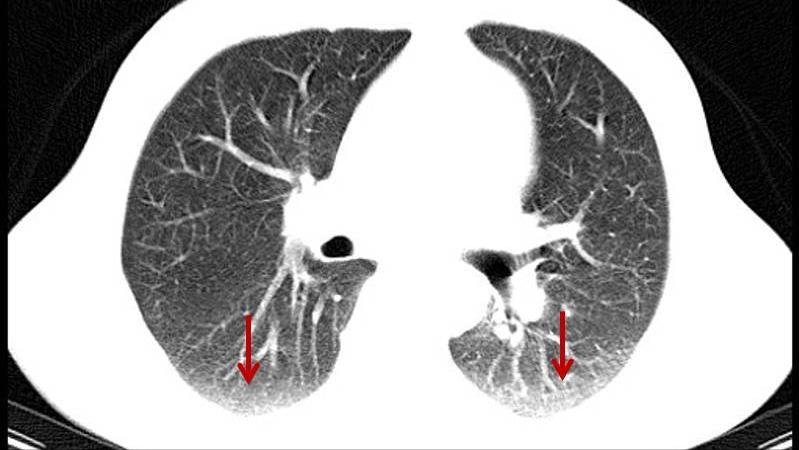

肺纹理是放射科的一个专业术语,是指胸部影像检查时所看到的从肺门向肺周围延伸的放射条状阴影。这种呈放射条状,像大树一样的阴影主要由我们刚刚说的肺动脉、肺静脉、支气管及淋巴管这些组织组成的。

肺纹理增多,在胸部影响检查下,发现从肺门到肺野外围延伸的这些呈放射状,像树枝一样的阴影正常人,有时增加。

值得注意的是,肺纹理在分布和形态上也会存在明显的个体差异,有些人的肺纹理可能会粗一些,而有些人的肺纹理可能会细一些。另外,影像检查的影响因素比较多,X线成像原理又比较复杂,人体的密度、厚度、X线穿透力、放射科医生的技术水平等可能都会影响到检查的结果,最后出现肺纹理增多的现象。